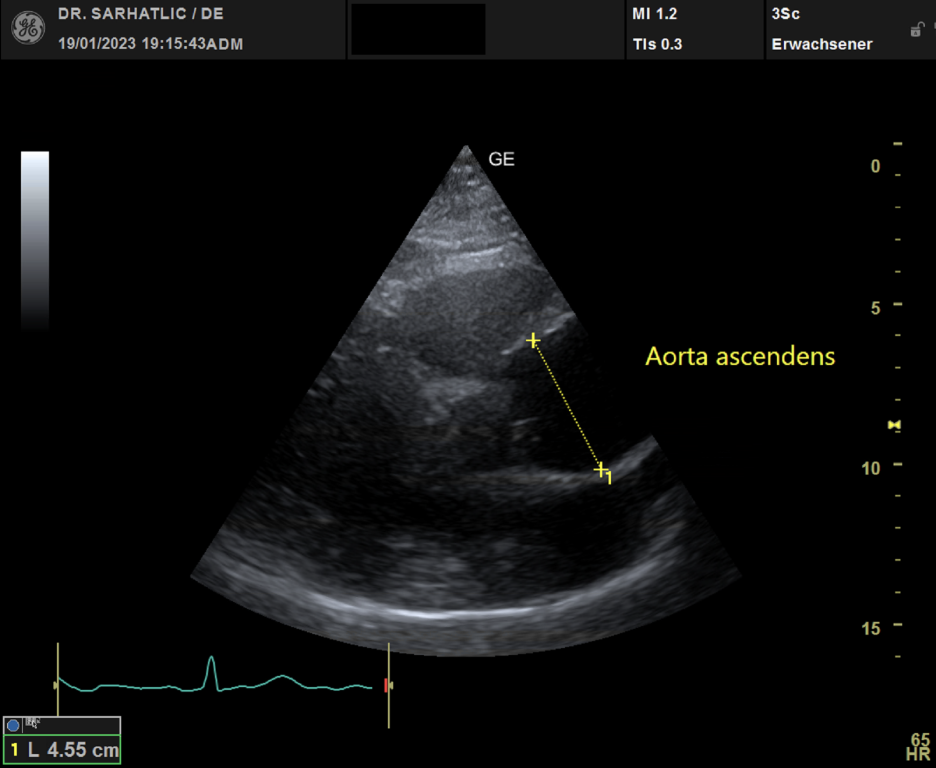

- Ultraschall des Herzens (Echokardiografie)

VORSORGE-SCHWERPUNKTE- Herz- & Kreislauf-Vorsorge

- Schlaganfallvorsorge (inkl. Gefäßdiagnostik)